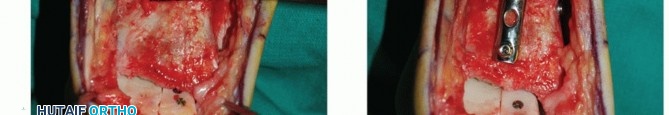

- TECH FIG 4 • (continued) D,E. A different patient with similar graft, excellent interference fit, and secured with a single screw. D. Screw is inserted in lag fashion. E. Screw head is countersunk. F-H. Reduction of the medial malleolar osteotomy. F. Screw fixation through the predrilled holes. G. Antiglide plate. H. Final fluoroscopic evaluation of graft and reduction of medial malleolar osteotomy. Despite optimal clinical fit of the graft, rarely does the fluoroscopic appearance suggest anatomic graft match to the native talus, typically due to differing cartilage thicknesses between the donor and the host. Although the screws may appear prominent, two-dimensional fluoroscopy is deceiving because the screws are countersunk below the articular surface of the graft and the talar dome is curved.

Place the two screws in the predrilled holes and tighten the screws.

Although not essential for healing, we favor placing an antiglide plate over the proximal aspect of the osteotomy.

Using fluoroscopy, confirm reduction of the graft and medial malleolus (see TECH FIG 4).

Anticipate some incongruencies of the graft-native talus bony interfaces. It is difficult to achieve perfectly congruent apposition.

There will be a slight gap at the medial malleolar osteotomy site despite anatomic reduction of the medial malleolus. This is due to the thickness of the saw blade. However, it is not acceptable to see a step-off at the osteotomy site where it enters the tibial plafond; this must be anatomic.

The slight gaps at the graft and medial malleolus do not typically impair healing and should obliterate with eventual remodeling.

Place the screws in lag fashion.

Countersink the screw heads below the articular surface (TECH FIG 4D,E).

Using fluoroscopy, confirm that the graft and hardware are in optimal position (TECH FIG 4F-H).

The graft will not look perfect fluoroscopically, but as long as the clinical appearance is acceptable, the outcome has a good chance to be favorable.

The hardware may appear slightly proud fluoroscopically despite being countersunk. The talar dome is not a flat plane, and therefore the screw may seem to be protruding. Moreover, the articular cartilage is rather thick compared to such a low-profile screw head.